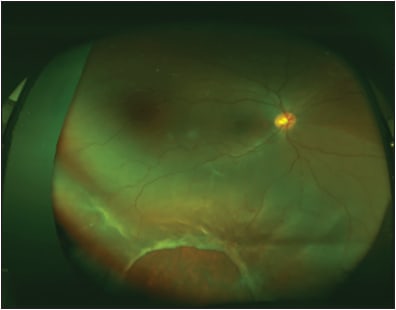

Widefield color fundus and fundus fluorescein angiogram images in Figures 1 and 2 illustrate the abnormal retinal vasculature, telangiectasias, hemorrhages, and exudative deposits characteristic in Coats disease. Laser photocoagulation with a wavelength of 532 nm was chosen for the treatment of this case of Coats disease.

Stickler syndrome is a connective tissue disorder associated with abnormal production of types II, IX and XI collagen.14 These patients have an increased rate of retinal tears and detachments that often manifest during childhood.15 Figure 3 includes fundus images of a patient with Stickler syndrome who required pars plana vitrectomy, endolaser, and silicone oil tamponade for rhegmatogenous retinal detachment associated with a giant retinal tear.